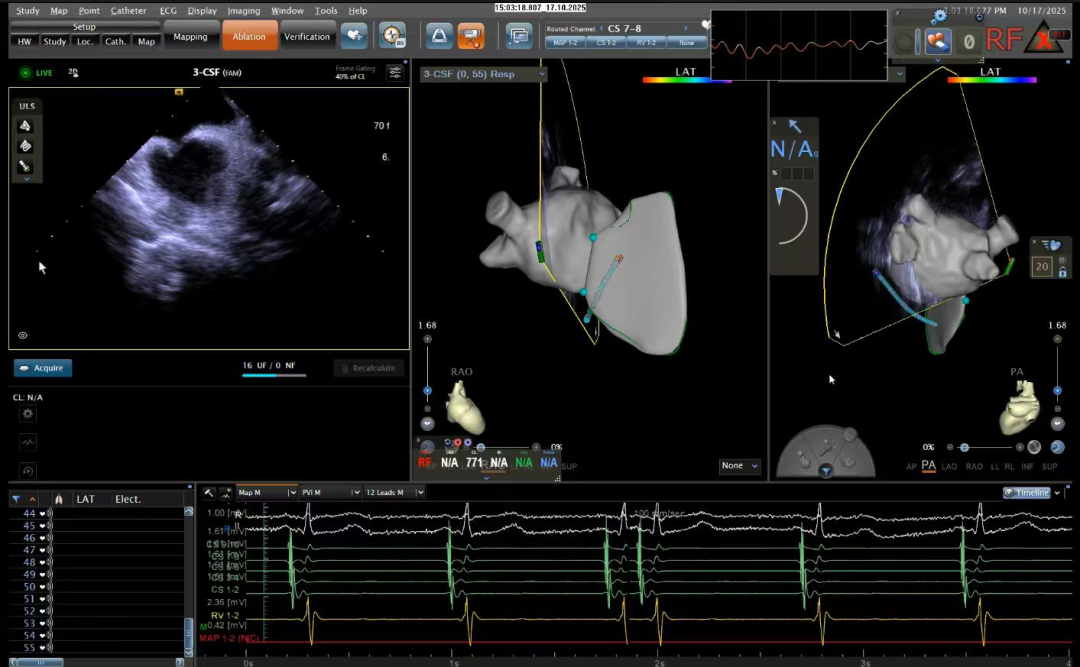

在心血管内科主任廉哲勋、病区主任李健的指导下,路军副主任医师、李姗副主任医师精准操作,配合三维心腔内超声引导进行标测与定位。随着射频能量的精准释放,异常电路被成功阻断,手术顺利完成。手术过程中,患者保持清醒,腹中胎儿一切正常,当听到手术成功的消息时,她流下了喜悦的泪水。

心腔内超声引导下房间隔穿刺

绿色射频消融手术采用的心脏三维电解剖标测系统,如同精密的“心脏GPS”,可在电脑上实时构建出患者心脏的立体模型,医生可通过股静脉将细小的消融导管送入心脏,在三维系统的精准导航下,迅速定位导致心动过速的“异常电路”(旁路或双径路),进行精准的射频消融。